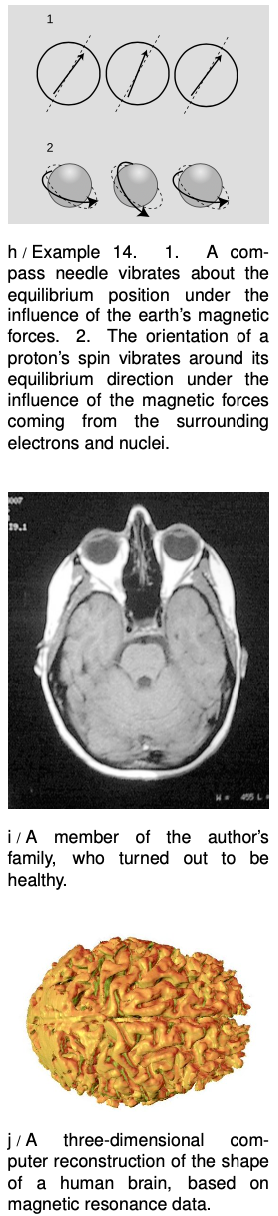

If you have ever played with a magnetic compass, you have undoubtedly noticed that if you shake it, it takes some time to settle down, h/1. As it settles down, it acts like a damped oscillator of the type we have been discussing. The compass needle is simply a small magnet, and the planet earth is a big magnet. The magnetic forces between them tend to bring the needle to an equilibrium position in which it lines up with the planet-earth-magnet.

Essentially the same physics lies behind the technique called Nuclear Magnetic Resonance (NMR). NMR is a technique used to deduce the molecular structure of unknown chemical substances, and it is also used for making medical images of the inside of people's bodies. If you ever have an NMR scan, they will actually tell you you are undergoing “magnetic resonance imaging” or “MRI,” because people are scared of the word “nuclear.” In fact, the nuclei being referred to are simply the non-radioactive nuclei of atoms found naturally in your body.

Here's how NMR works. Your body contains large numbers of hydrogen atoms, each consisting of a small, lightweight electron orbiting around a large, heavy proton. That is, the nucleus of a hydrogen atom is just one proton. A proton is always spinning on its own axis, and the combination of its spin and its electrical charge causes it to behave like a tiny magnet. The principle is identical to that of an electromagnet, which consists of a coil of wire through which electrical charges pass; the circling motion of the charges in the coil of wire makes it magnetic, and in the same way, the circling motion of the proton's charge makes it magnetic.

Now a proton in one of your body's hydrogen atoms finds itself surrounded by many other whirling, electrically charged particles: its own electron, plus the electrons and nuclei of the other nearby atoms. These neighbors act like magnets, and exert magnetic forces on the proton, h/2. The `k` of the vibrating proton is simply a measure of the total strength of these magnetic forces. Depending on the structure of the molecule in which the hydrogen atom finds itself, there will be a particular set of magnetic forces acting on the proton and a particular value of `k`. The NMR apparatus bombards the sample with radio waves, and if the frequency of the radio waves matches the resonant frequency of the proton, the proton will absorb radio-wave energy strongly and oscillate wildly. Its vibrations are damped not by friction, because there is no friction inside an atom, but by the reemission of radio waves.

By working backward through this chain of reasoning, one can determine the geometric arrangement of the hydrogen atom's neighboring atoms. It is also possible to locate atoms in space, allowing medical images to be made.